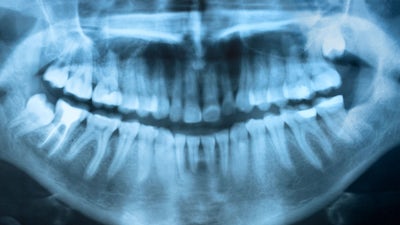

Is chronic mercury poisoning from amalgam fillings adversely affecting our health? Yes, says dentist and naturopath Alison Adams, who shares her personal recovery story.